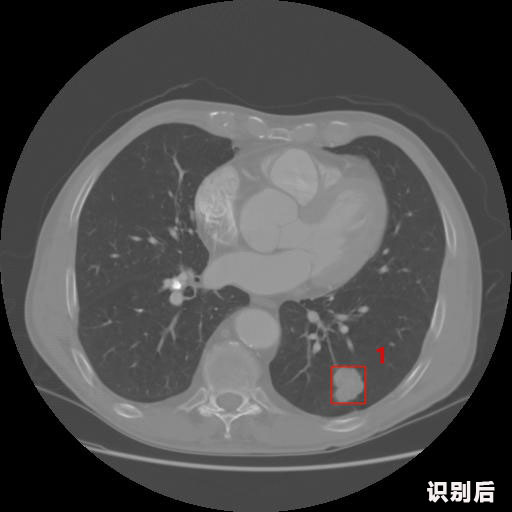

英特健康AI深度學習醫(yī)療圖像識別系統(tǒng)案例_胸部CT

報告:

1.發(fā)現(xiàn)肺結節(jié)的可能性為95.56%---位于框指數(shù)位置:[331.70554 366.13406 365.21707 403.96234]